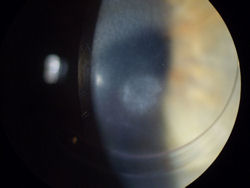

Изображение: ФРК была выполнена на этом глазу за год до того, как была сделана фотография. У пациента развилось постоянное помутнение центральной части роговицы, что привело к значительному ухудшению зрения.